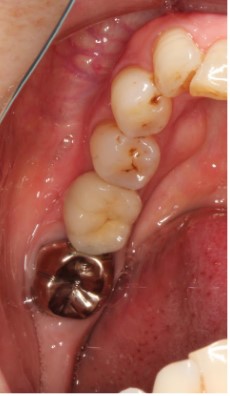

2024.12.1540代男性 天然歯をできる限り残すためにインプラントを用いながら虫歯の治療と噛み合わせを改善した症例